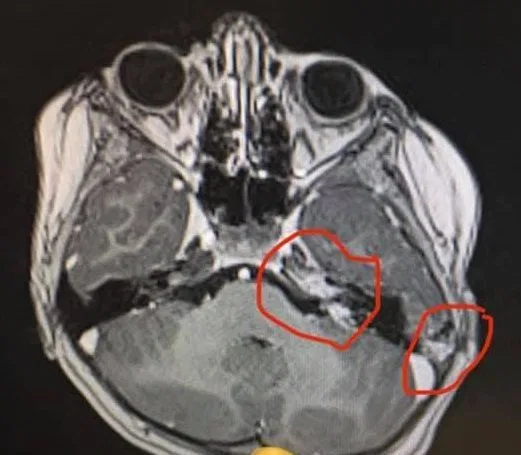

“She spent the night being observed in Wishaw and the CT scan results came the following day and confirmed her diagnosis,” Jemma wrote on Facebook. “She had not one, but THREE puss filled abscesses on her cerebellum which were putting pressure on her optic nerve, hence the squint/dizziness/double vision etc.

“Caused by a bacterial infection which probably entered her brain through the ear (remember her ear infection a few weeks previous which we thought had cleared up?) She needed immediate treatment, but Wishaw was not equipped for this kind of condition.”